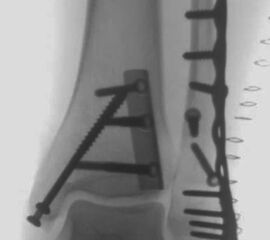

Die Versorgung von AO 44-B Frakturen erfolgt über einen längsverlaufenden lateralen Zugang. In der Regel gelingt eine suffiziente Stabilisierung mittels interfragmentärer Zugschraube (bei langem Frakturverlauf ggf. 2 Zugschrauben) und einer zusätzlichen Neutralisationsplatte (Abbildung 9 & 10).

Bei multifragmentären Frakturen (AO 44-B2.3) oder bei schlechter Knochenqualität sollte die Versorgung mittels winkelstabiler Plattenosteosynthese erwogen werden (Abbildung 11 & 12).